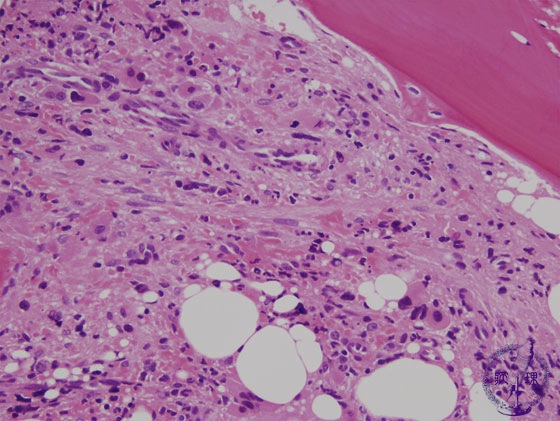

- 1.Bone marrow / Hematopoietic system

- (6) Myeloproliferative disorders (Polycythemia vera)

Microscopic image (H&E high power view): Fibroblasts are also proliferating in the hypercellular marrow. As with fibroblasts proliferation, marked deformity is observed in hematopoietic cells. Megakaryocytes are numerous. The pale pink fibrous tissue is found in the background.